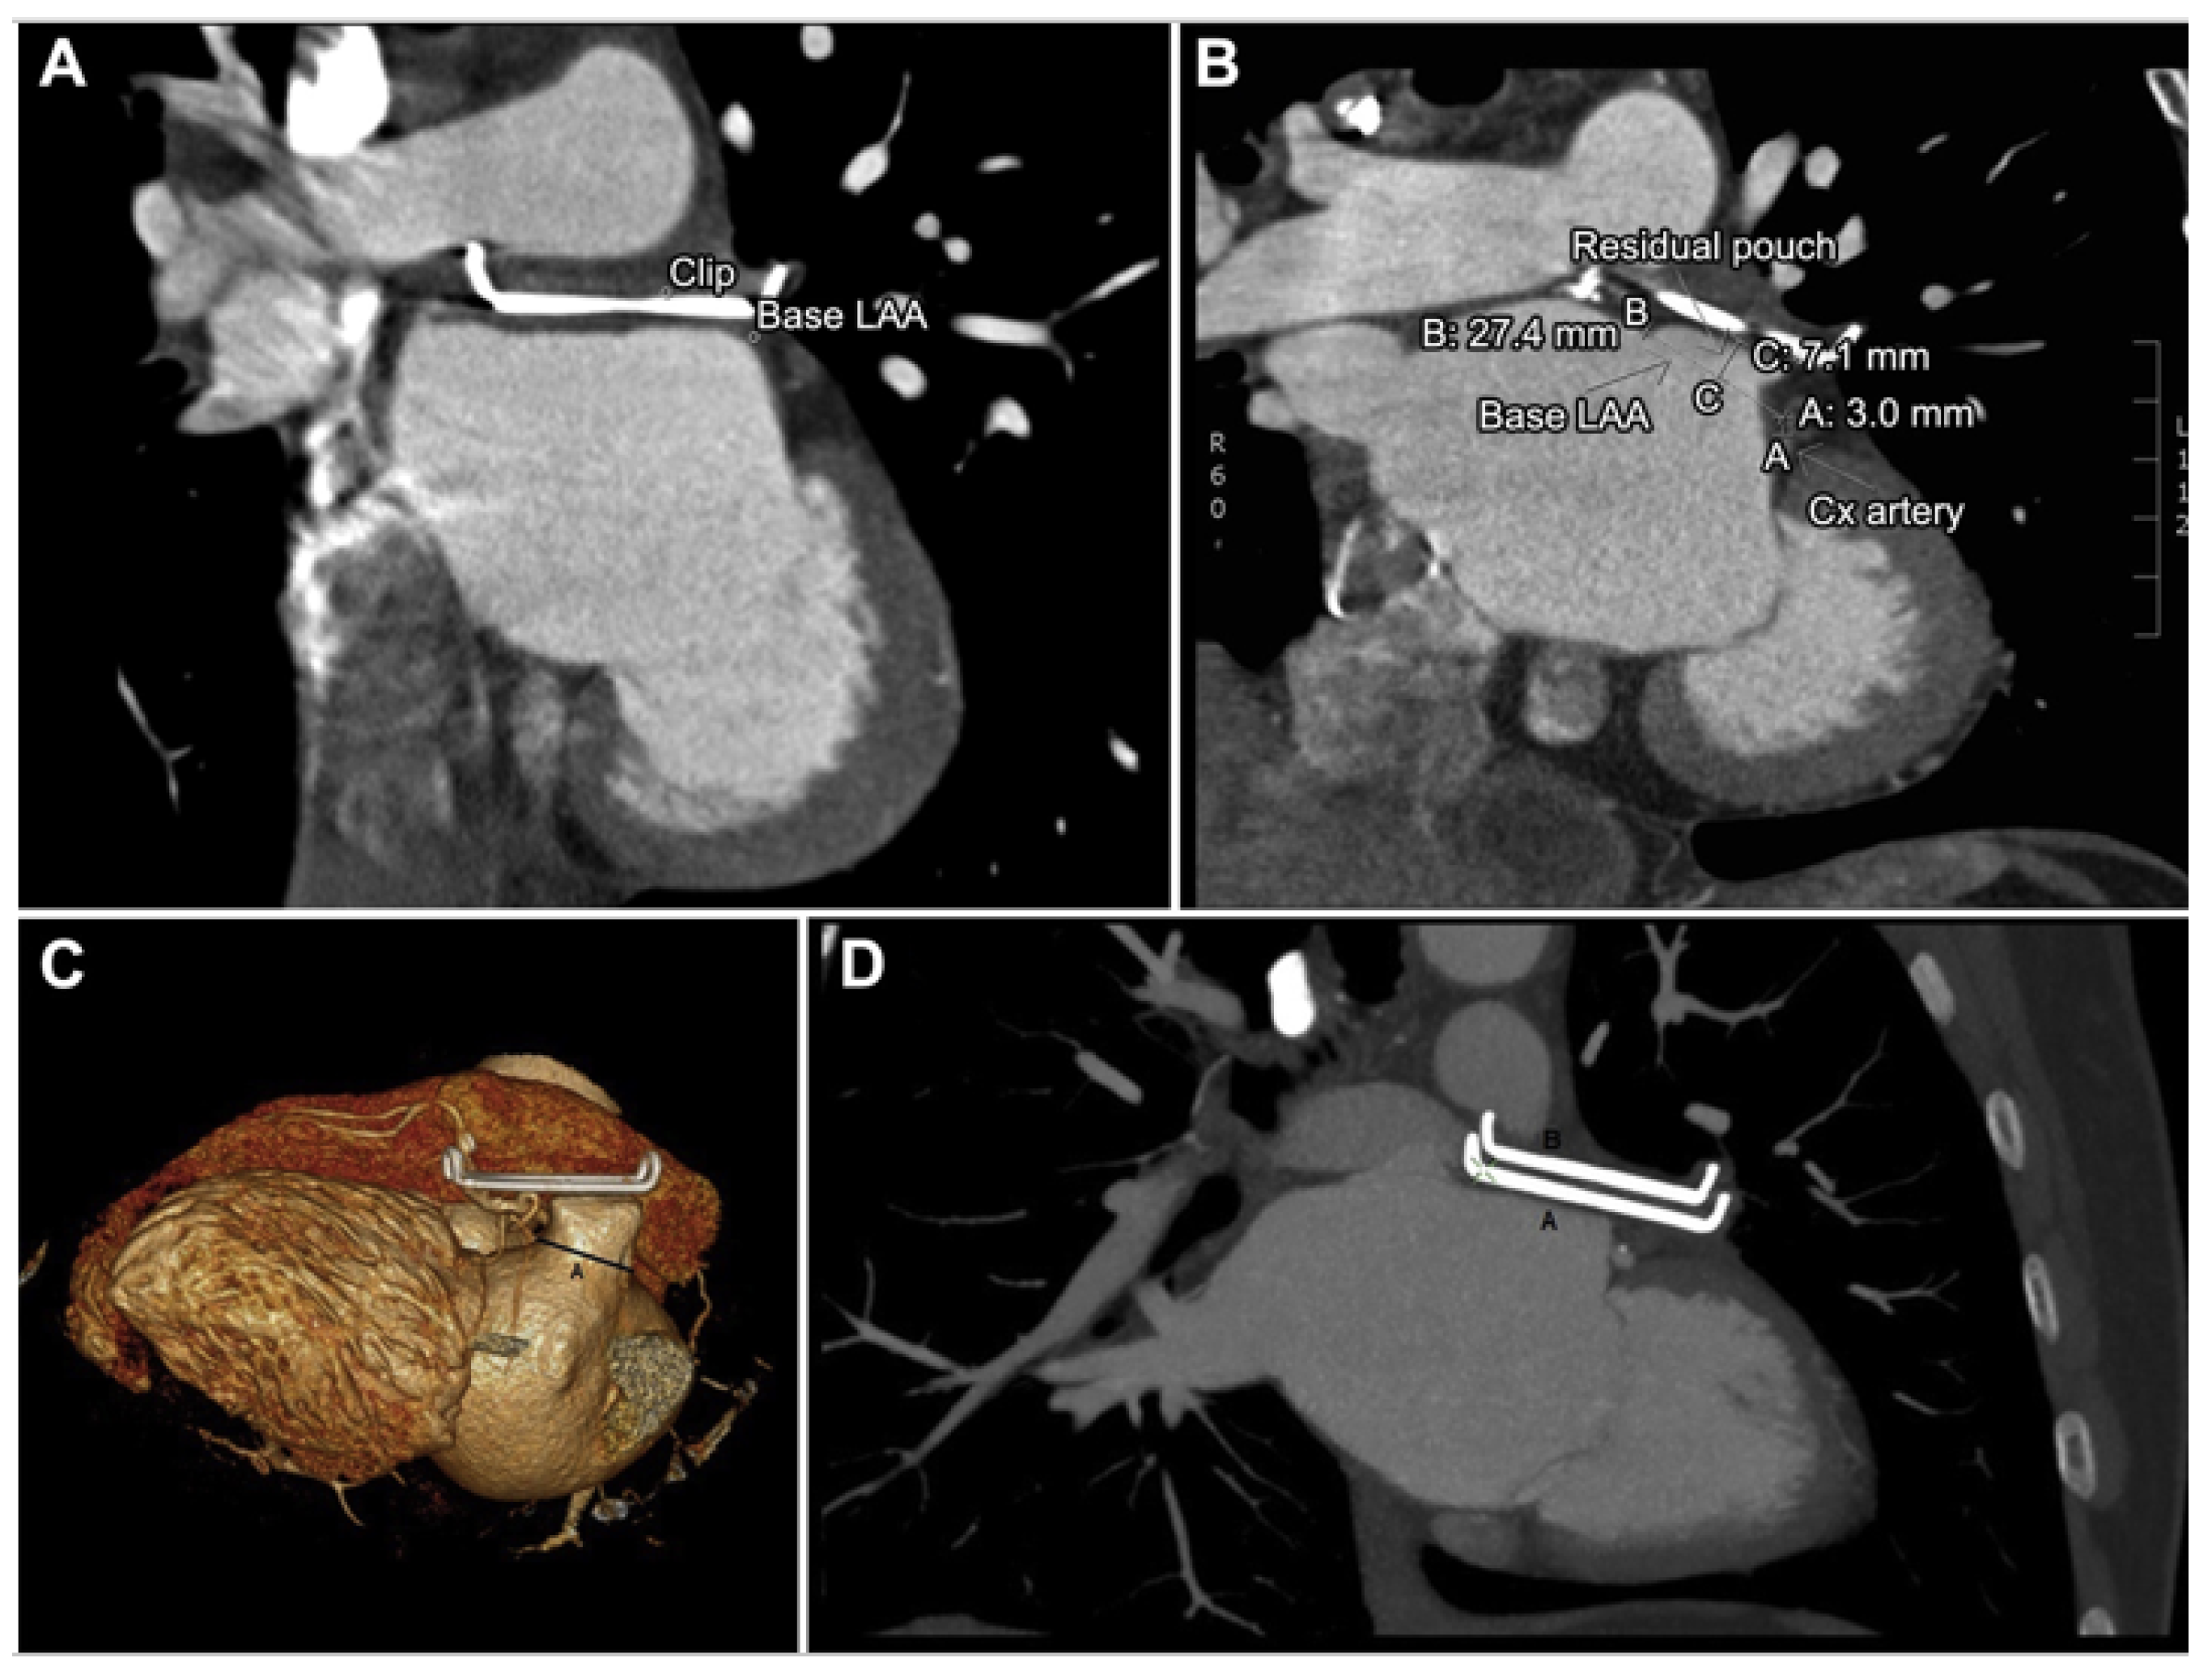

3.5. Epicardial Devices